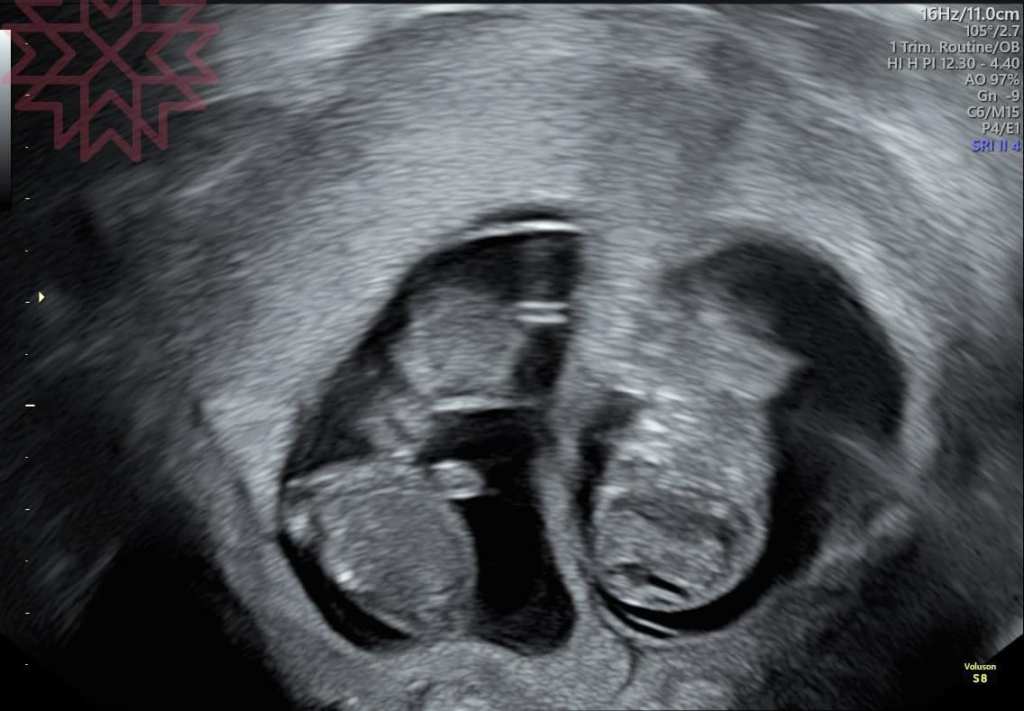

直接看圖

只要專業的醫師大概在這時候都可以知道哪一個是單絨毛膜雙羊膜哪一個是雙羊膜雙絨毛膜

2

單絨毛膜雙羊膜(MCDA)雙胞胎

這個一定是同卵

因為共用胎盤所以比較會有血流養分分配不均的問題

這個追蹤的重點最主要是在於雙胞胎輸血症候群

所以我會建議在中期以前要比較密集的追蹤

早期發現早期治療

對了

隨便挑三張

抽考一下

大家看得出來這裡面分別有幾個羊膜幾個絨毛膜嗎?

答案之後公佈